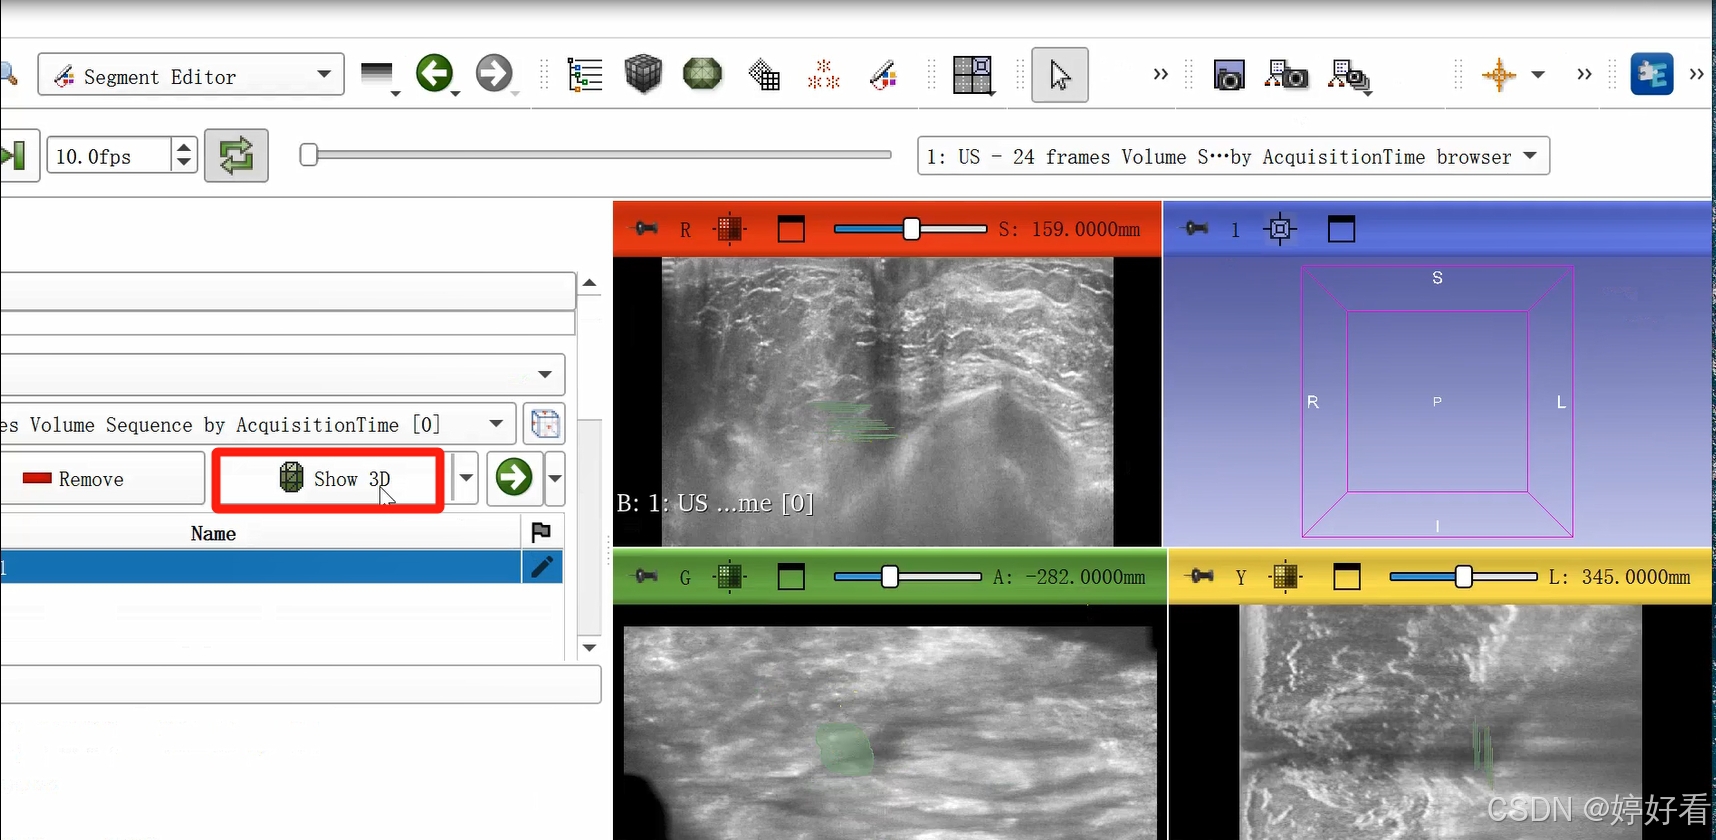

2.4 点击Show 3D,显示三维图像。

2.5 选中以下居中的符号,使绘制好的三维图像居中。